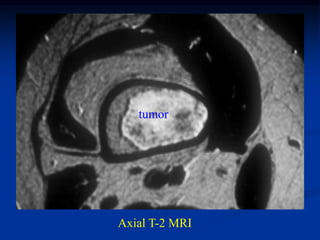

Axial T-2 MRI

Tumor seen thru cortical window